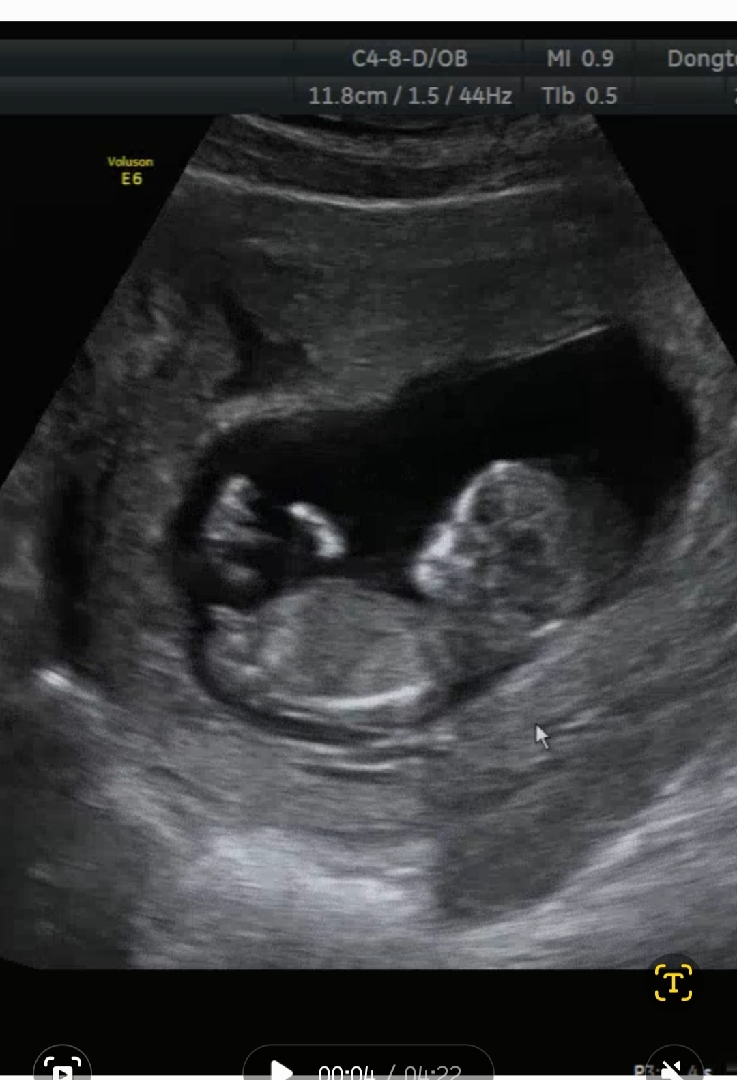

각도법 고수님들 초음파 사진좀 봐주세요 !! 11주 5일차 사진입니다.!!